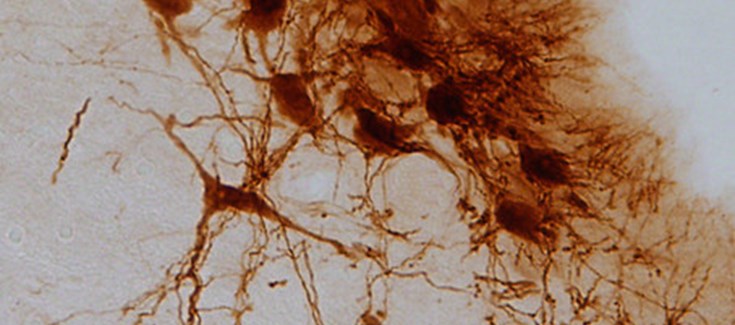

Neuronas de locus cerúleo. / Fundación Descubre

Sin embargo, este desarrollo se manifiesta en el cerebro mediante procesos diferentes. Cuando el dolor se origina por una diabetes mal controlada, este se refleja en el sistema nervioso central a través de una disminución en la producción de noradrenalina y una disfunción en la actividad del locus cerúleo, una región anatómica en el tallo cerebral involucrada en la respuesta al pánico y al estrés.

El locus cerúleo es el principal productor de noradrenalina del cerebro, una biomolécula involucrada en la transmisión del mensaje nervioso entre las neuronas y que desempeña un papel importante en la ansiedad y la depresión.